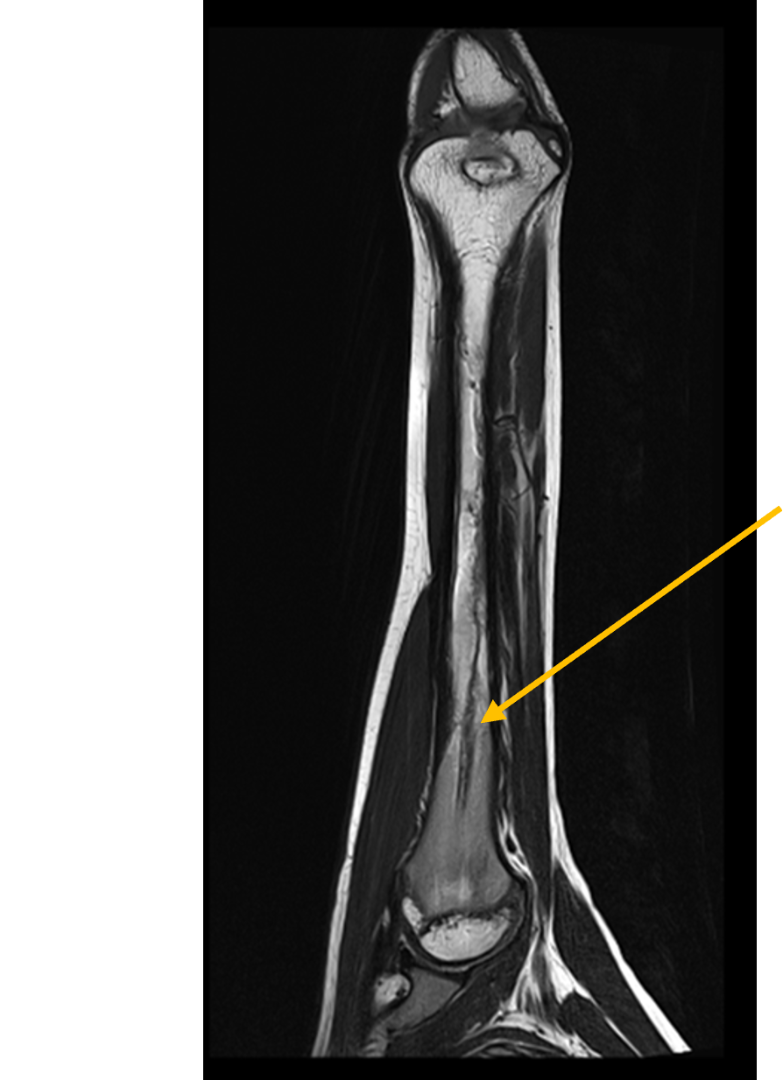

- (A,B) : MR LEFT FOREARM

- B 1 : Tract of previous intramedullary nail seen in shaft of humerus, along with mild diffuse cortical thickening.